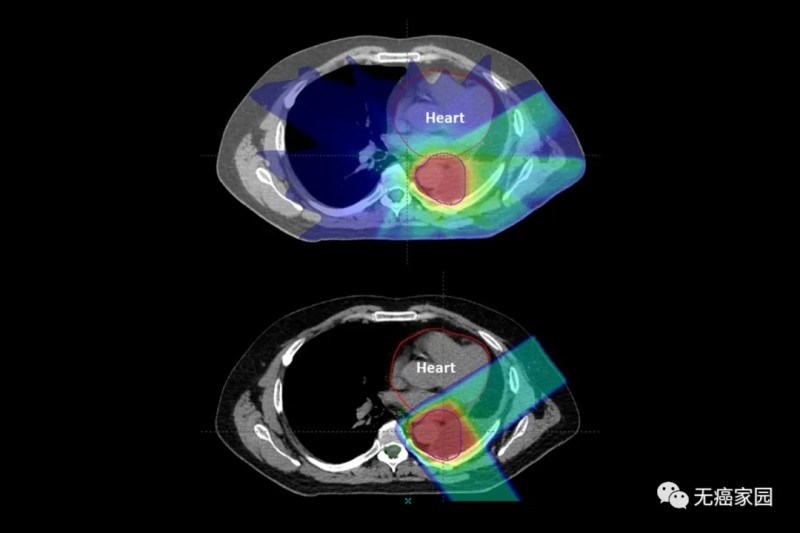

图中病例为肺部肿瘤,质子治疗(底部)在击中肺部肿瘤后停止,X射线(顶部)由光子组成,这些粒子会穿过身体并损伤健康组织(图中为心脏)结果显示,质子治疗组一年的总体生存率为83%,而X射线放疗组为81%,并无明显差异。

但两种疗法的副作用差异十分明显:在90天内,质子治疗组中有45名患者(11.5%)出现了严重的副作用症状,而X射线放疗组有301名患者(27.6%)在同一时期出现了严重副作用症状。

这种差异还是在质子治疗组患者平均年龄更大且存在更多医疗问题情况下出现的。研究人员称,剔除这些差异因素影响,接受质子治疗的患者在90天内出现严重副作用症状的风险要比接受X射线放疗的患者低67%(2/3)。